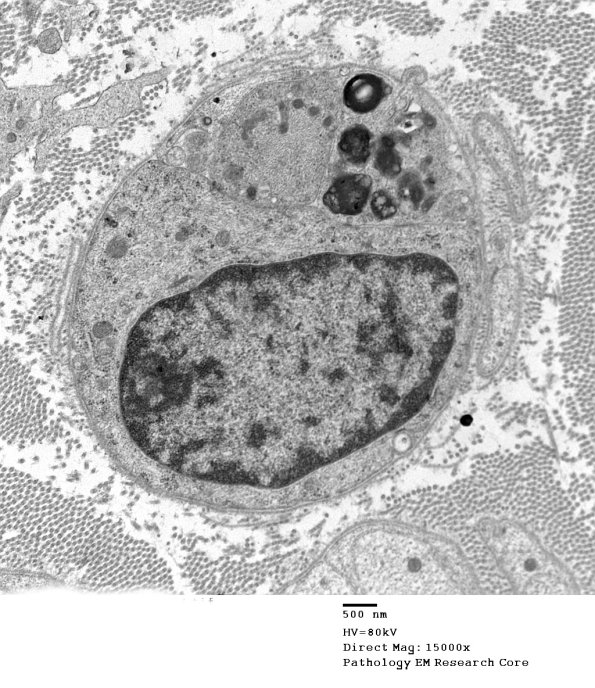

2F5A,B The nucleated cell is a Schwann cell which no longer myelinates the axon in its cytoplasm. A process containing myelin debris likely belongs to a macrophage, a portion of which extends a process outside of the Schwann cell.. (electron micrograph)